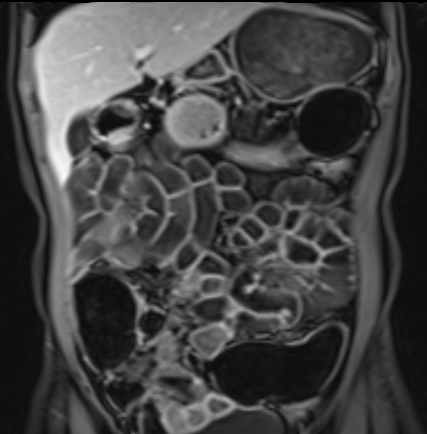

Ruột non bình thường, nhưng ghi nhận các đoạn hẹp ở đại tràng xuống và đại tràng ngang.

Cả hai đoạn hẹp đều có thành ruột dày đến 8 mm và ngấm thuốc rõ rệt theo kiểu niêm mạc ở đại tràng xuống và kiểu phân lớp ở đại tràng ngang.

Giãn ruột trước chỗ hẹp được ghi nhận ở cả hai đoạn.

Do các chỗ hẹp này không hiện diện khi nội soi đại tràng trước khi điều trị kháng TNF, nhiều khả năng chúng đã hình thành trong quá trình điều trị.

Do đó, quyết định phẫu thuật cắt đại tràng gần toàn bộ với miệng nối hồi-sigma đã được đưa ra.